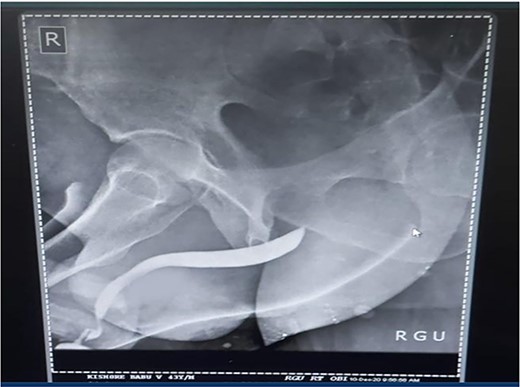

A 37-year-old male presented with a history of a ‘snap’ sound and immediate detumescence of penis during intercourse, when he fell and hit the pubic bone of his partner. There was generalized swelling and pain in the penis. There was acute retention of urine, an attempt to pass a catheter failed and the patient underwent supra-pubic catheterization. On examination, there was classical ‘eggplant deformity’ of the penis with blood at the tip of the meatus. MRI showed a tunical tear on both sides at the penoscrotal junction with indistinct urethra and extensive hematoma in the proximal penile shaft (Fig. 1). With the diagnosis of a fractured penis and possible urethral injury, after proper counselling, the patient was taken up for surgery. On the table, a retrograde urethrogram (RGU) was done showing evidence of partial urethral disruption. On exploration with penoscrotal vertical incision, there was total transection of proximal penile urethra, and a 1.5 cm tunical injury of corpus cavernosum on both sides ventrally (Fig. 2). There was extensive hematoma. Corpora sutured with 4.0 prolene after reconstructing the midline septum. Urethral ends mobilized and anastomosed with 3.0 vicryl in a single layer with minimal spatulation (Fig. 3). The patient was discharged on the 5th post-operative day; Foley catheter was removed on day 21. Follow-up RGU done after 3 months showed no evidence of stricture (Fig. 4).

Follow-up RGU done after 3 months showing no evidence of stricture.

Penile fracture is an uncommon urological emergency that occurs when the tunica albuginea in an erect penis rupture due to excessive external bending stress during sexual activity and the injury is most caused at the time of coitus [1, 2]. Other less common causes are masturbation and the practice of Taqaandaan [3, 4]. In most cases, a penile fracture results in a cracking sound, fast detumescence, abrupt enlargement and ecchymosis of the penis, which gives it the appearance known as ‘eggplant deformity’ [5]. The rupture occurs more often in the proximal shaft and is located ventrally in coital injuries. In our case, there was a bilateral corporal tear. Literature states that bilateral corporal ruptures are often accompanied by urethral injury [6]. Urethral rupture, although infrequent, has an incidence that varies between 1 and 38%. This rupture may be partial or complete [7, 8]. Blood in the meatus, hematuria and voiding symptoms are highly indicative of urethral rupture, but the absence of these findings does not exclude urethral lesions [9]. Our patient presented with swelling, pain and acute retention of urine, which was followed by a failed attempt at urethral catheterization and on examination of the penis, we found blood at the tip of the meatus. All these findings yielded a high suspicion of urethral injury and we decided to perform an RGU. In suspected cases of urethral injury, RGU may demonstrate contrast leakage at the lesion site and reveal the exact point of urethral injury. However, RGU can show false negative results in up to 28.5% of cases [10]. In this case report, RGU could only show evidence of a partial rupture but, intraoperatively, there was found to be a complete transection of the proximal penile urethra. Compared to the traditional non-operative options, surgical restoration of the tear has proven to provide patients with the greatest results in terms of both sexual function, cosmetic appearance and fewer complications [9, 11, 12]. Penile degloving using a circumferential or subcoronal incision is the most used technique followed by penoscrotal and longitudinal incisions directly over the hematoma. The sub-coronal degloving incision is useful in cases with significant penile swelling or extensive hematomas, as well as in cases where the location of tunical rupture cannot be determined clinically or radiographically, or when the rupture is located dorsally [13]. Major disadvantages of the sub coronal degloving incision are the extensive dissection of Buck’s fascia and its risk of distal penile/preputial skin necrosis. In this case, we performed a penoscrotal incision. We chose this technique because it gives easy exposure to the base of the corpora cavernosa where fractures tend to occur more often and in addition would give us direct access to the urethral transection. With the penoscrotal incision, we have the flexibility of extending the incision and can also avoid futile dissection in the buck’s fascia [13]. We reconstructed the midline septum and closed the corpora using 4.0 prolene. Urethral ends were mobilized and anastomosed with 3.0 vicryl in a single layer with minimal spatulation. The patient was discharged on the 5th postoperative day, and the Foley catheter was removed on day 21. A follow-up RGU performed after 3 months showed no evidence of stricture.